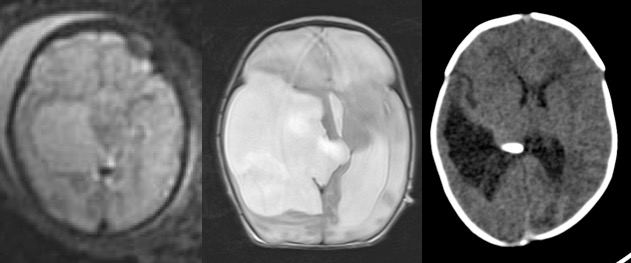

les kystes de l’incisure tentorielle

ces kystes , souvent diagnostiqués en anténatal, sont souvent quiescents et ne nécessitent pas de traitement.

lorsqu’ils progressent, ils s’accompagnent le plus souvent d’une hydrocéphalie et une intervention endoscopique est envisageable ; le geste consiste à fenêtrer le kyste dans les ventricules.

visionner l’endoscopie pour kyste de l’incisure tentorielle

en l’absence d’hydrocéphalie, la valve kyste-péritonéale reste une option satisfaisante ; c’est le recours en cas d’échec ou de complication de l’endoscopie.